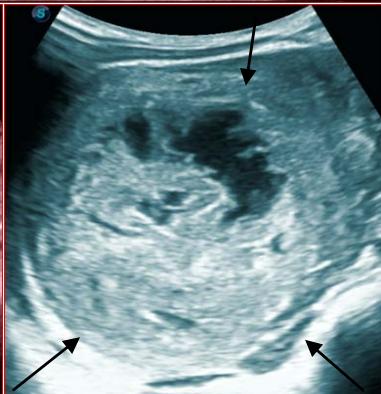

Figure 5: Abdominopelvic ultrasound control after 6 courses of chemotherapy in the same 3 year old patient with a ruptured left renal nephroblastoma; Images A, F, G, and H: show regression of the solid, endo and exo renal, left nephroblastoma mass treated with 6 courses of chemotherapy (current volume 430 ml vs) Images: B, C, and: show persistence of thrombotic permeation pan vena cava and ipsilateral renal. Image E: shows a volumetric regression of the intra-lesional hematic collection, at the tumor rupture estimated at 34.49 ml VS, Image I: represents the right kidney in B mode which is of normal echoculture. Source: Dr. Frederick Tshibasu Tshienda database.